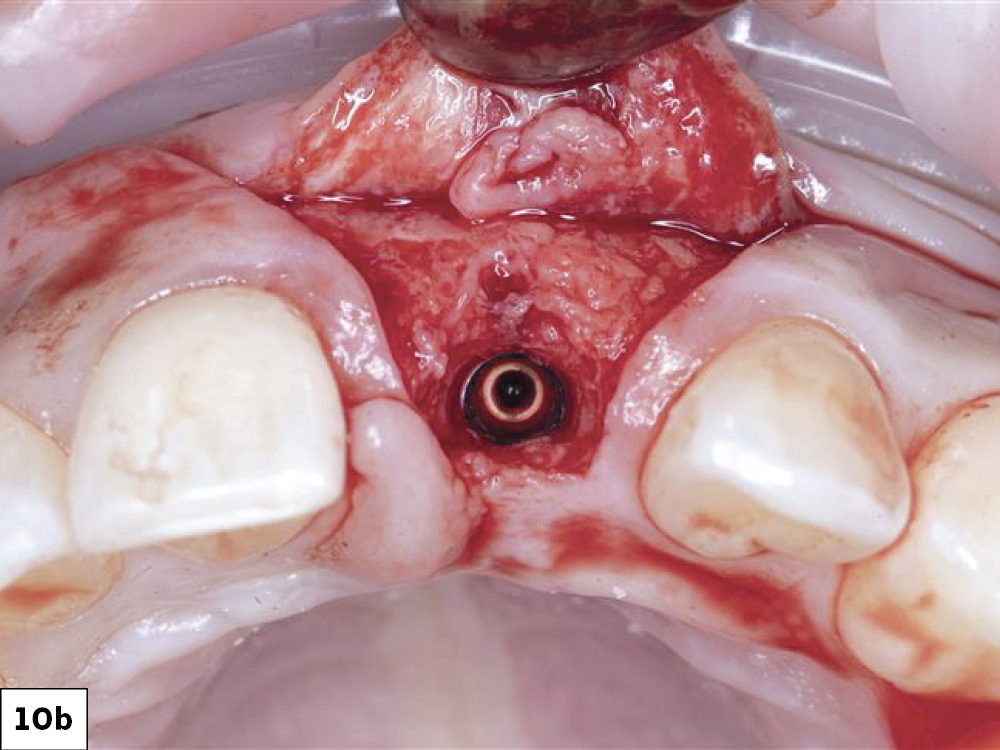

When I met with Raquel, she had just completed aligner therapy. We discussed the space discrepancy between tooth #8 and the site for #9, and we agreed that the best solution was a partial coverage composite to reshape #8 and an implant-supported restoration to replace tooth #9.

A Glidewell HT™ Implant (Glidewell Direct; Irvine, Calif.) was chosen because it offers excellent primary stability, a clinically proven success rate and a simple surgical protocol. BruxZir® Esthetic Zirconia was chosen for the final crown because of its combination of strength and lifelike esthetics.